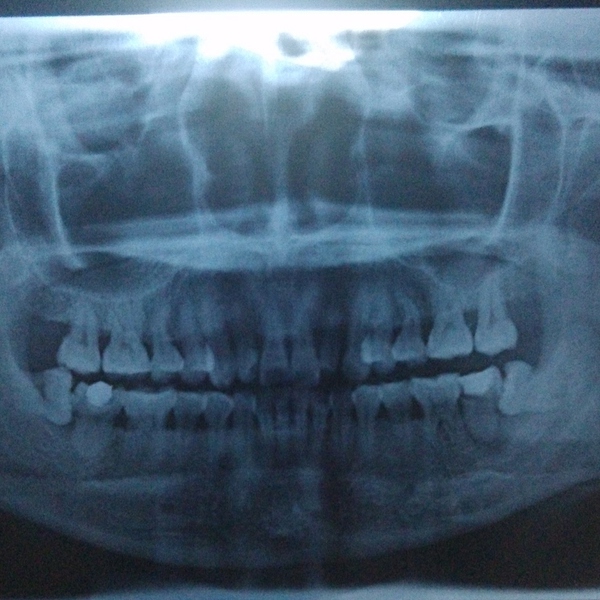

牙齿萌出困难称为"阻生齿"或"埋伏牙"。阻生齿最常见于下颌第三磨牙,俗称智齿,此牙萌出年龄在18岁前后,因为萌出前其它牙齿都早已站好队列了,等智齿生长出来时,就会受到其它牙齿的排挤,故而萌出困难,形成了阻生齿或埋伏牙,我们称之为"阻生智齿"。

首先并不是每个人都有机会萌出全部四颗智齿,如果某一颗没有对生的,有可能会造成对位的口腔黏膜磨损,多见于下位。 其次,阻生智齿一定要拔除。阻生简而言之就是你的口腔骨骼没有给那颗牙留足够的位置,这样智齿就会用把兄弟姐妹往旁边挤的粗暴方式长出来。这个过程中,任何的外界刺激,食物残渣残留都可能造成严重感染,

这种情况下就一定要先消炎然后拔除。否则以后你每次发烧感冒都可能使智齿感染,反过来也一样。 一般来说阻生智齿拔除不是大手术,上牙比下牙好拔除,但依据你的牙齿状况,过程可能持续10到15分钟,一定会打麻药,麻药负责你那半边脸的痛感缺失。手术过程中首先要划开牙龈,然后非常可能用到锤子和其他工具把牙撬出,或如果你的牙形比较细长,可能直接敲碎拿镊子夹出。手术风险:如果你的牙根非常长,长到和其下的神经有粘连,可能导致局部的永久性麻痹。术后:每个医生都会告诉你多久拿掉填充物多久可以刷牙。